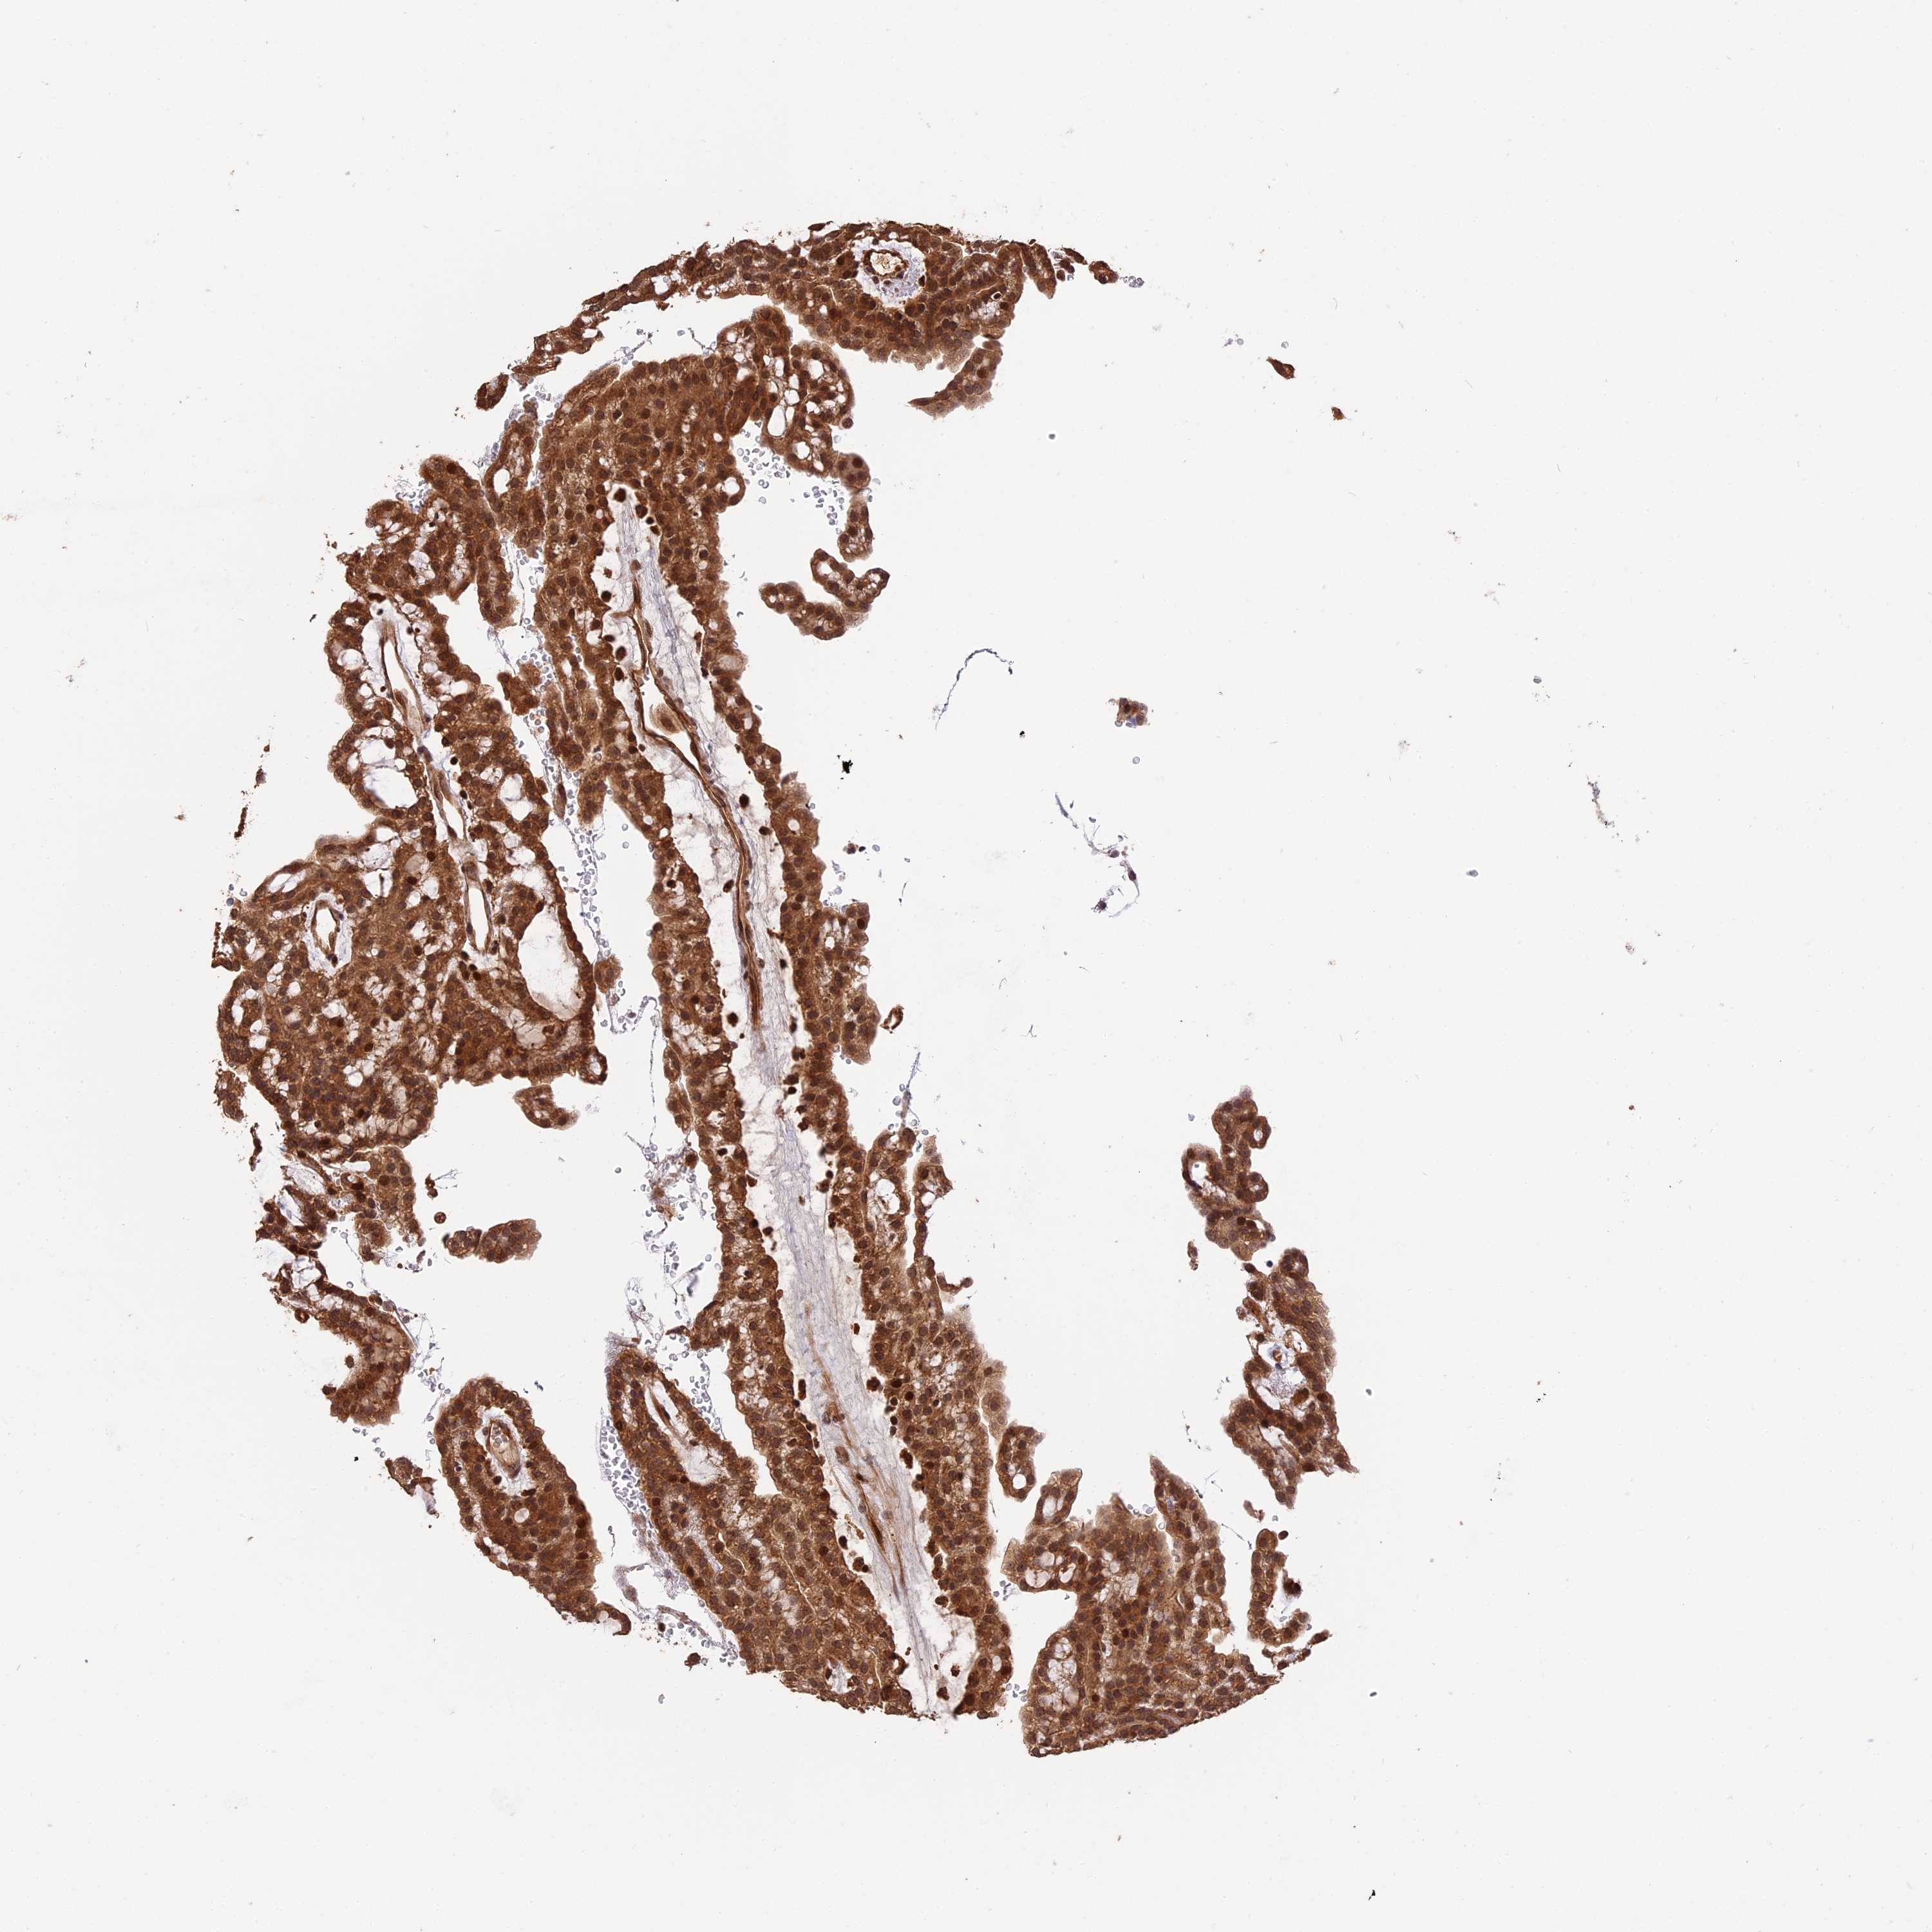

TCGA RNA samplesi

RNA-seq data is reported as average FPKM (number Fragments Per Kilobase of exon per Million reads), generated by the The Cancer Genome Atlas (TCGA) .

Normal distribution across the dataset is visualized with box plots, shown as median and 25th and 75th percentiles. Points are displayed as outliers if they are above or below 1.5 times the interquartile range. FPKM values of the individual samples are presented next to the box plot.

Average pTPM 10.0

Number of samples 100